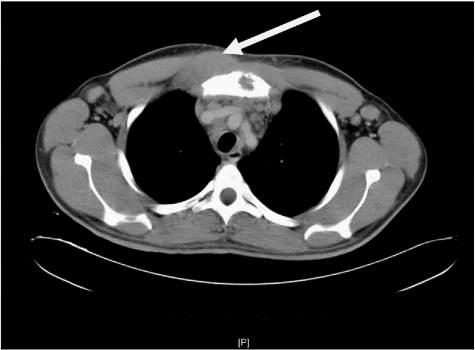

Fig.1.12 Computedtomographyscanofapatientcomplainingofrightcostosternalpainrevealinga rightchestwallmassatthelevelofthesecondrib (arrow).(FromRichBS,McEvoyMP,Honeyman JN,etal.Hodgkinlymphomapresentingwithchestwallinvolvement:acaseseries. JPediatrSurg 2011;46(9):1835 1837[Fig.2].ISSN0022-3468, https://doi.org/10.1016/j.jpedsurg.2011.05.015, http://www.sciencedirect.com/science/article/pii/S0022346811004428.)